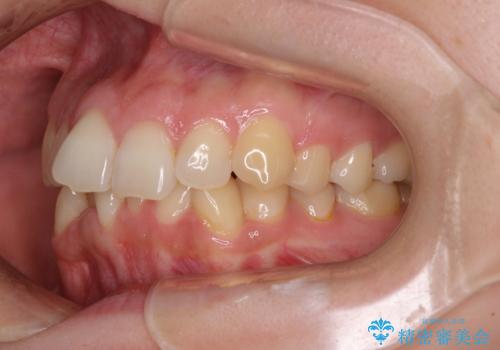

左右ともに、上顎第二大臼歯が欠損しており、下顎の第二大臼歯が十分に咬み合う歯がない状態のため、放置しておくと下顎の奥歯が挺出してくる可能性があります。

安定した咬み合わせを維持するためにも、将来的に上左右にインプラント補綴が必要となります。